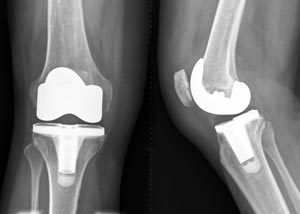

What does this x-ray show?

These are radiographs of an unknown patient taken at an unknown time. They show antero-posterior and lateral views of the patient’s right knee. The most pertinent finding is that there is a well-aligned, cemented total knee replacement. There does not appear to be any peri-prosthetic fractures visible. There are no signs of any other fractures, nor of osteoarthritis (though this may have been an indication for the TKR). In summary, these are AP and lateral radiographs of a patient with a right TKR.

TLDR: Well-aligned, cemented TKR with no peri-prosthetic fractures